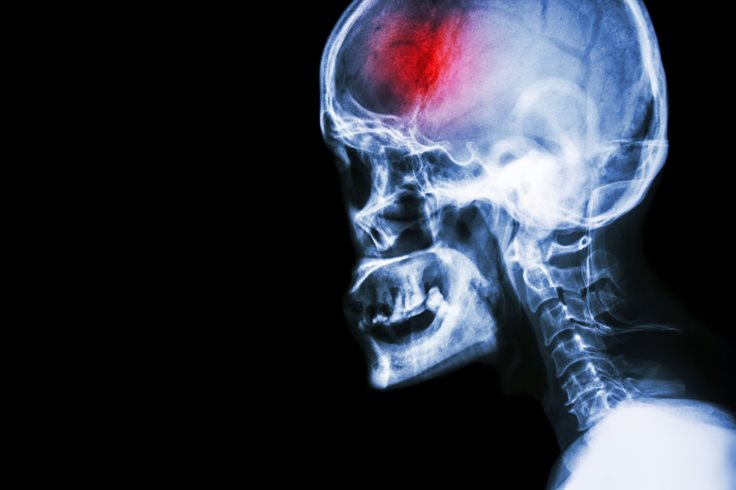

• Stroke: 6.24 million deaths per year.[4][5]

• Death Causes Stroke

Strokes occur when the blood supply to the brain is cut off by a blood clot. Time is crucial when dealing with a stroke victim, as brain cells begin to die within minutes, and, unless treated, death follows swiftly after.